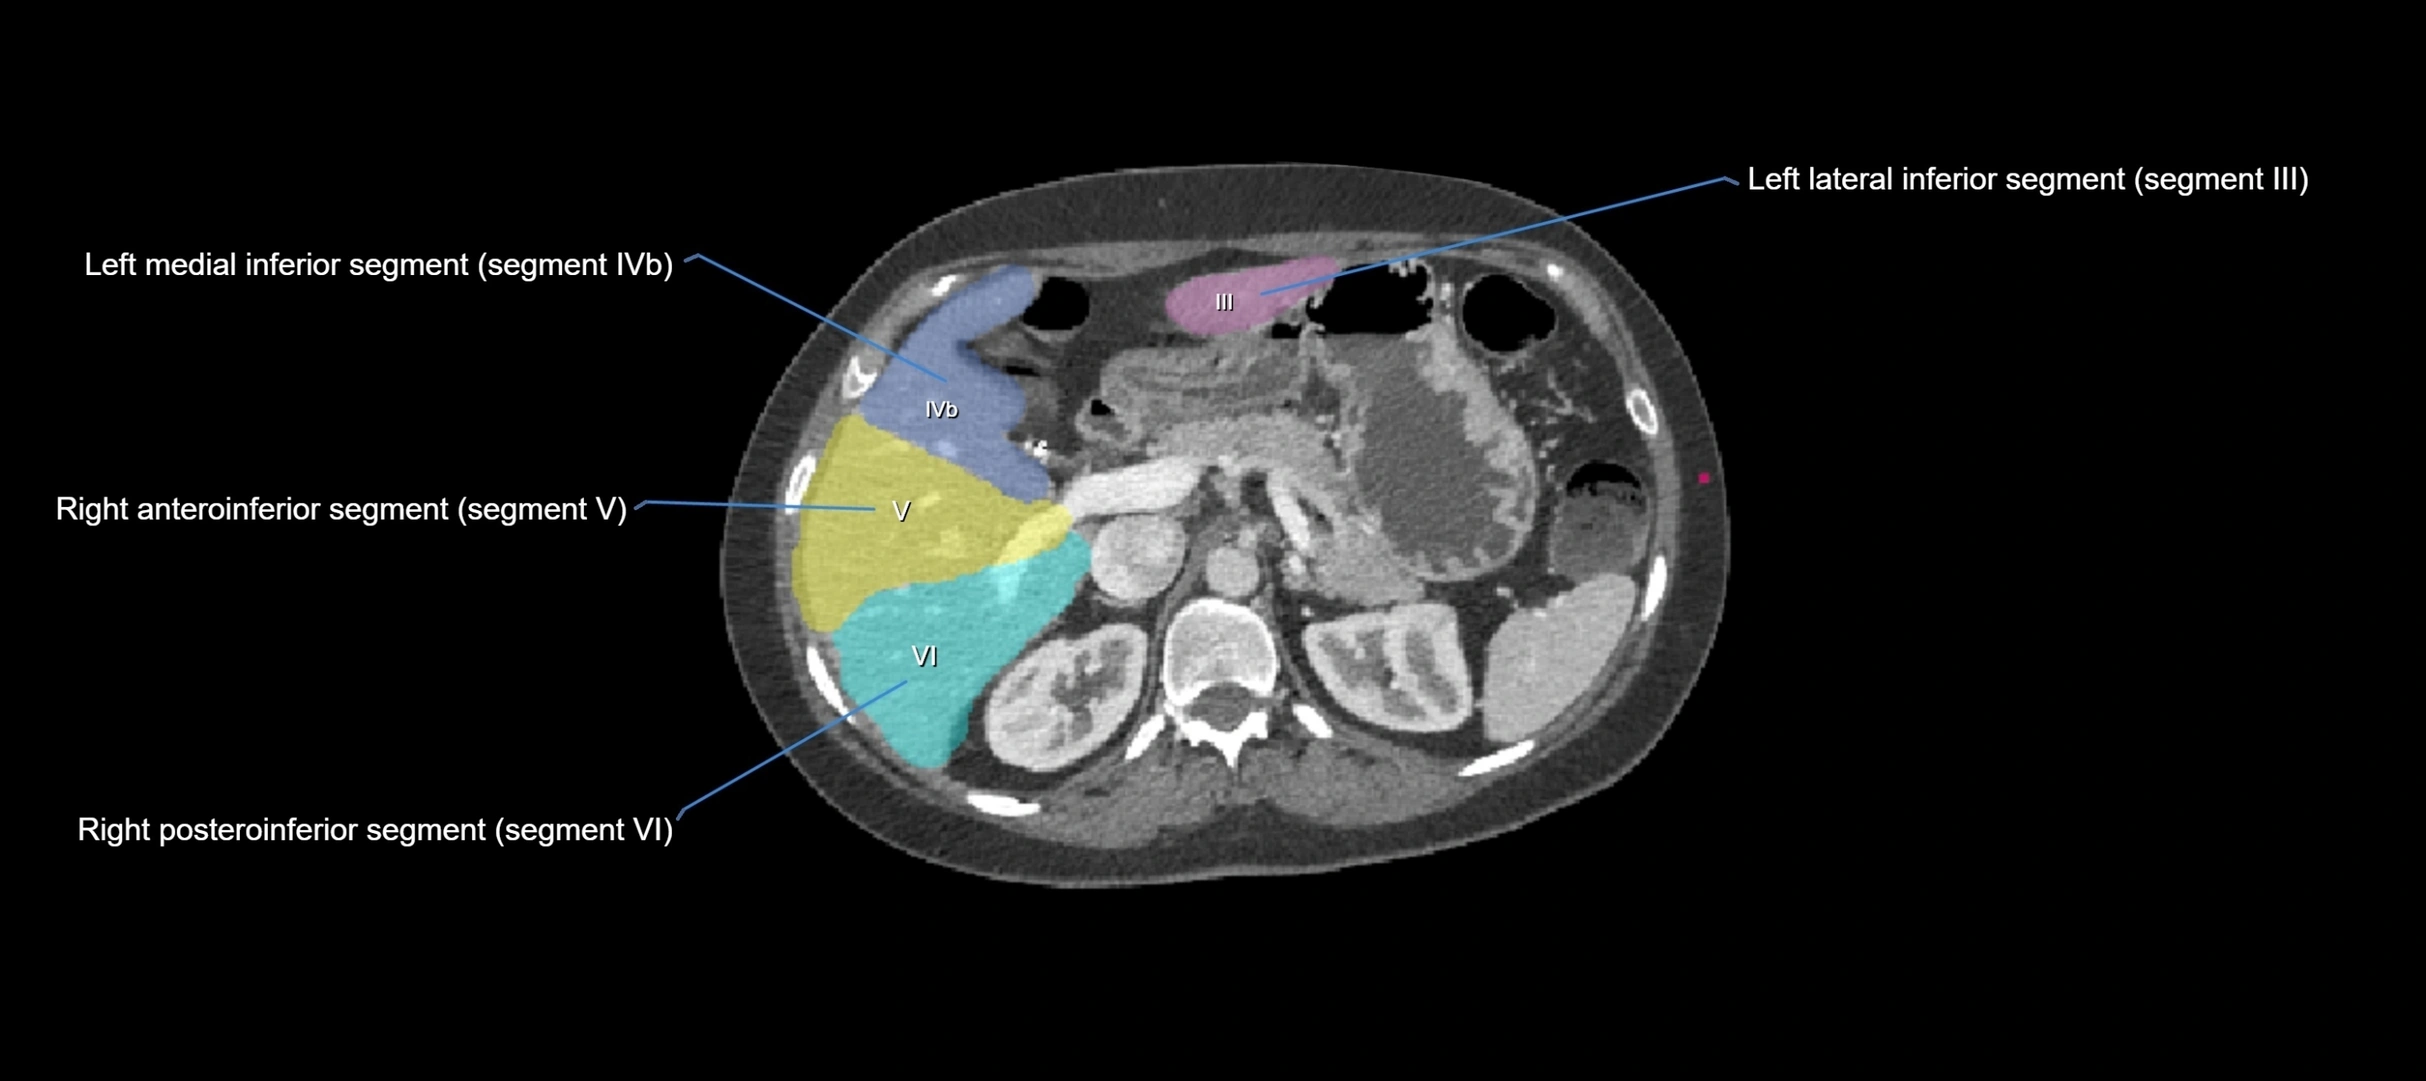

CT Appearance

CT Pre-Contrast:

• Caudate lobe appears as a soft-tissue density, isodense to the rest of the liver

• Enlargement may be appreciated in cirrhosis or Budd–Chiari syndrome

CT Post-Contrast:

• Homogeneous enhancement in the portal venous phase, similar to rest of liver

• Independent venous drainage into the IVC may be visualized

• Lesions follow characteristic CT enhancement patterns (HCC: arterial hyperenhancement with washout; hemangiomas: peripheral nodular enhancement with centripetal fill-in)

CT Venous Phase (functional significance):

• Caudate lobe often enhances relatively more than other lobes in Budd–Chiari syndrome, due to preserved venous outflow

CT Image

image